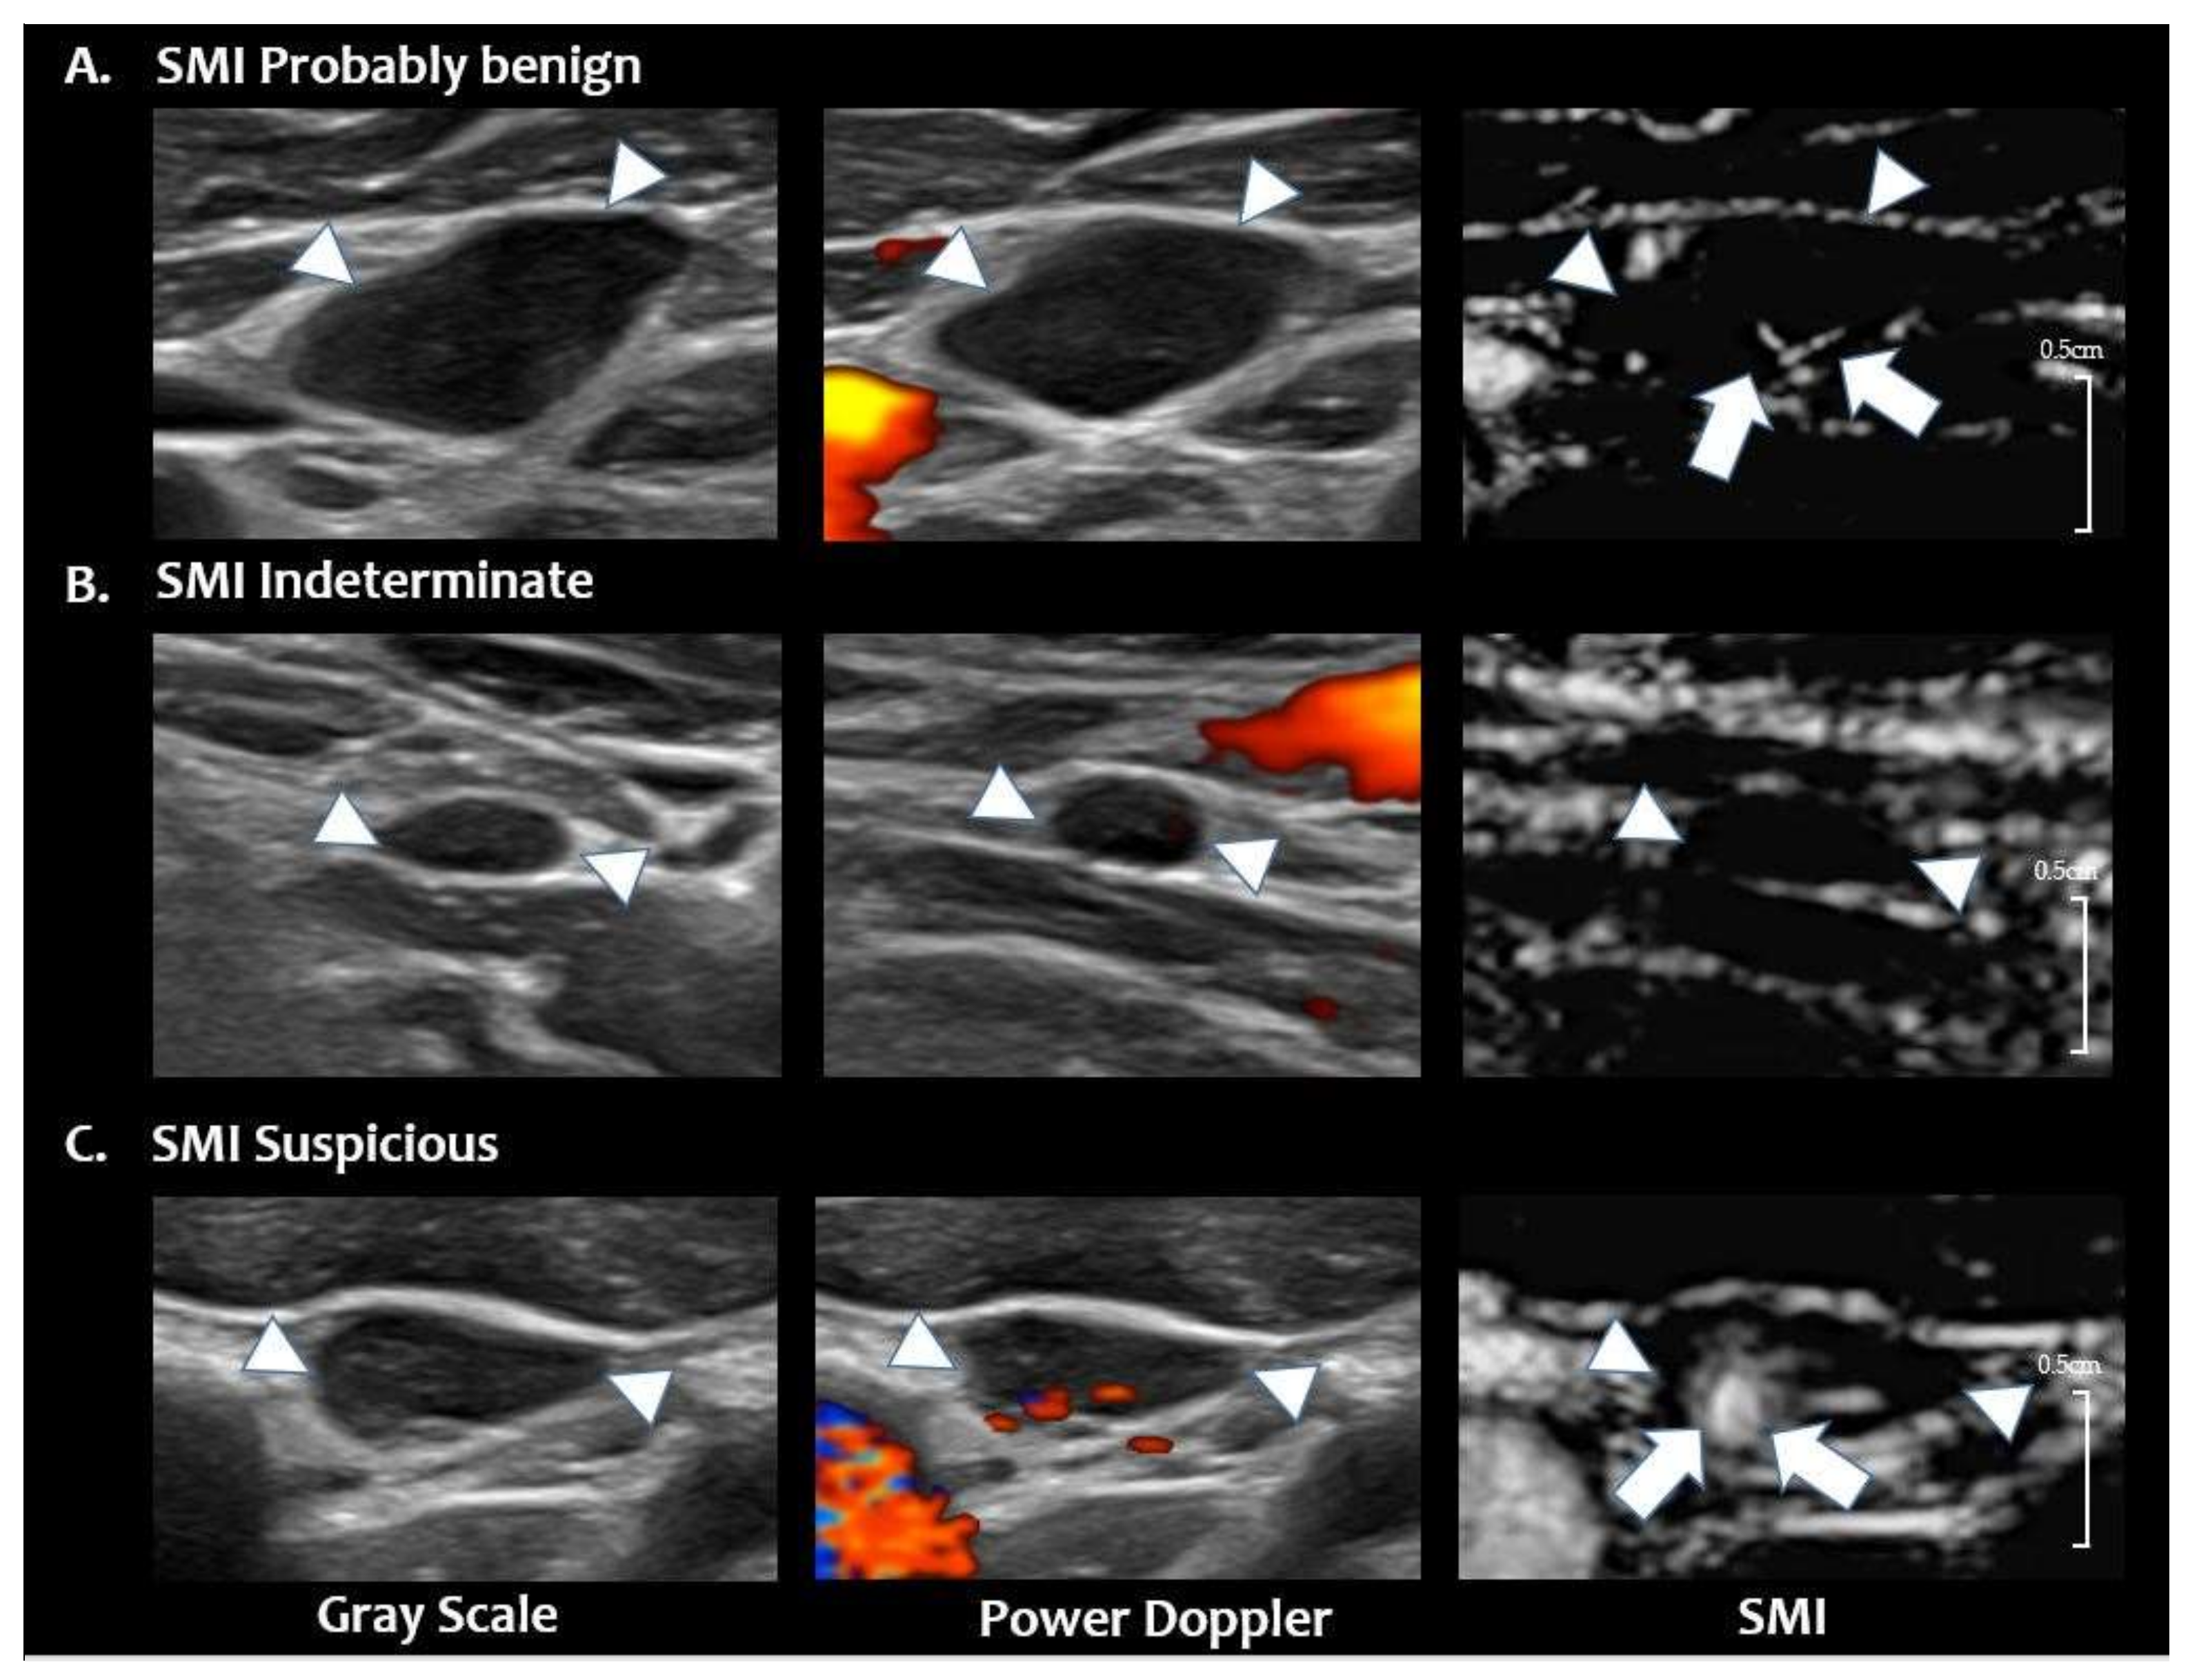

| Category | Numbers (%) | Malignancy Risk (%) |

|---|---|---|

| Probably benign | 26 (32.5) | 5/26 (19.2) |

| Indeterminate | 20 (25.0) | 4/20 (20.0) |

| Suspicious | 34 (42.5) | 32/34 (94.1) |